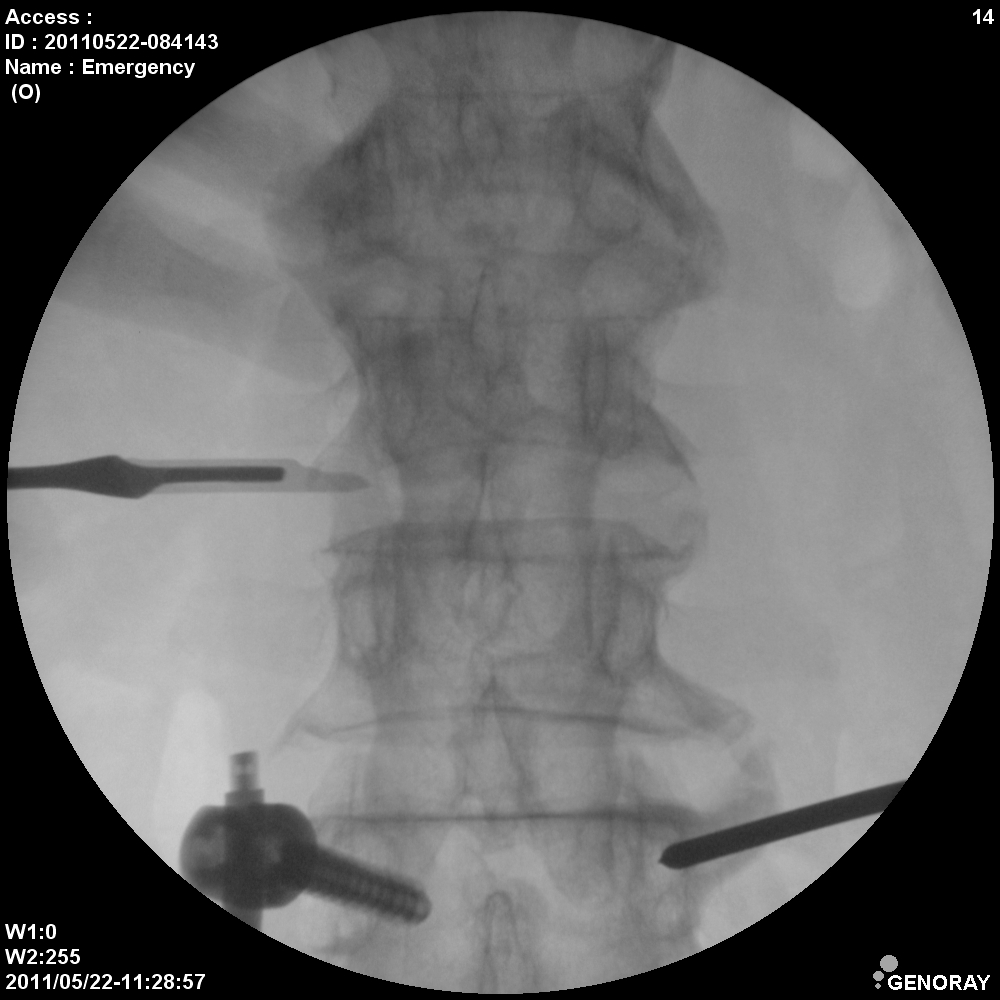

Аппарат применяется в различных областях медицины, таких как хирургия, ортопедия, педиатрия, травматология, урология и многих других. «РЕНЕКС-ОПТИМАЛ» имеет широкий диапазон перемещения и легко позиционируется во всех направлениях.

В качестве приемника используется усилитель рентгеновского изображения (УРИ) с ПЗС-матрицей 1024х1024 пикселей. Мощность рентгеновского питающего устройства 5,3 кВт. Система принудительного воздушного охлаждения, позволяет эффективно использовать аппарат на протяжении долгого времени без перегрева. Широкий диапазон регулирования количества импульсов при импульсной рентгеноскопии позволяет значительно снизить лучшею нагрузку, при этом при необходимости возможно проводить исследования с частотой до 30 кадров в секунду. С-дуга оснащена интерактивной сенсорной панелью управления всеми параметрами исследования на штативе аппарата.

- Непрерывная и импульсная рентгеноскопия с цифровой обработкой изображения.

- Цифровая рентгенография.